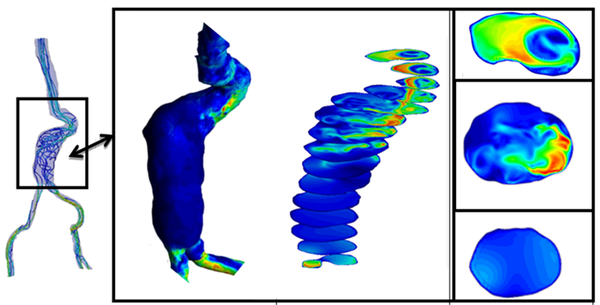

1.2.1.3 Aortic Aneurysms

The aortic dilatation is an asymptomatic disease with complicated and lethal sharp pains that can occur anywhere in the human aorta. By definition, if the aorta diameter at least is 50% greater than the normal size of the aorta produces what is called aneurysm. And if this occurs in the thoracic aorta is termed a Thoracic Aortic Aneurysm(TAA), in the abdominal aorta is named Abdominal Aortic Aneurysm(AAA). However, the aneurysm pathogenesis is still unknown.

|

| Figure 7: Diagnostic Indicators in Aortic Abdominal Aneurysm. Streamlines, wall shear stress and velocity profiles at different sections of the aneurismatic sac. |

It is thought that the initial dilatation is caused partly by degeneration of the medial elastin and smooth muscles in the arterial wall or by the effect of the wall shear stress. Vessel wall remodeling as a result of shear stress alteration is accompanied by synthesis and secretion of NO, growth factors and metalloproteins, which contribute to aneurysm pathogenesis. Genetics and risk factors like smoking, hypertension, chronic obstructive pulmonary disease(COPD), inflammation and atherosclerosis play key roles in aneurysms genesis and progression[49]. In this context, there are few predictors of the aorta dilatation available in the clinical practice. Mainly, they are based on the aortic diameter and increasing aortic size. Currently, the accepted values have been changing over time and they are actually being discussed by the groups with experience, for example, [50][51] in TAA patients or [52][53] in AAA patients. There is also a hemodynamic factor of parietal stress in the aortic dilatation, which is currently a little-known factor. Prior works, related TAA, have confirmed the presence of different flux in bicuspid aortic valve without aortic dilation compared to tricuspid aortic valves patterns by using cardiac magnetic resonance imaging (cardiac MRI). Abnormal flow patterns have been also detected in aneurysms located in the ascending aorta which confirms flow jets to the anterolateral wall of the aorta [54]. It is also known that shear stresses play an important role in the initiation, progression and rupture of aneurysms[55][56]. Vorticity inside the aneurysm is connected to aneurysm plaque or thrombus formation [5][11]. Figure 7 shows some DI's in an Aortic Abdominal Aneurysm(AAA)[15].